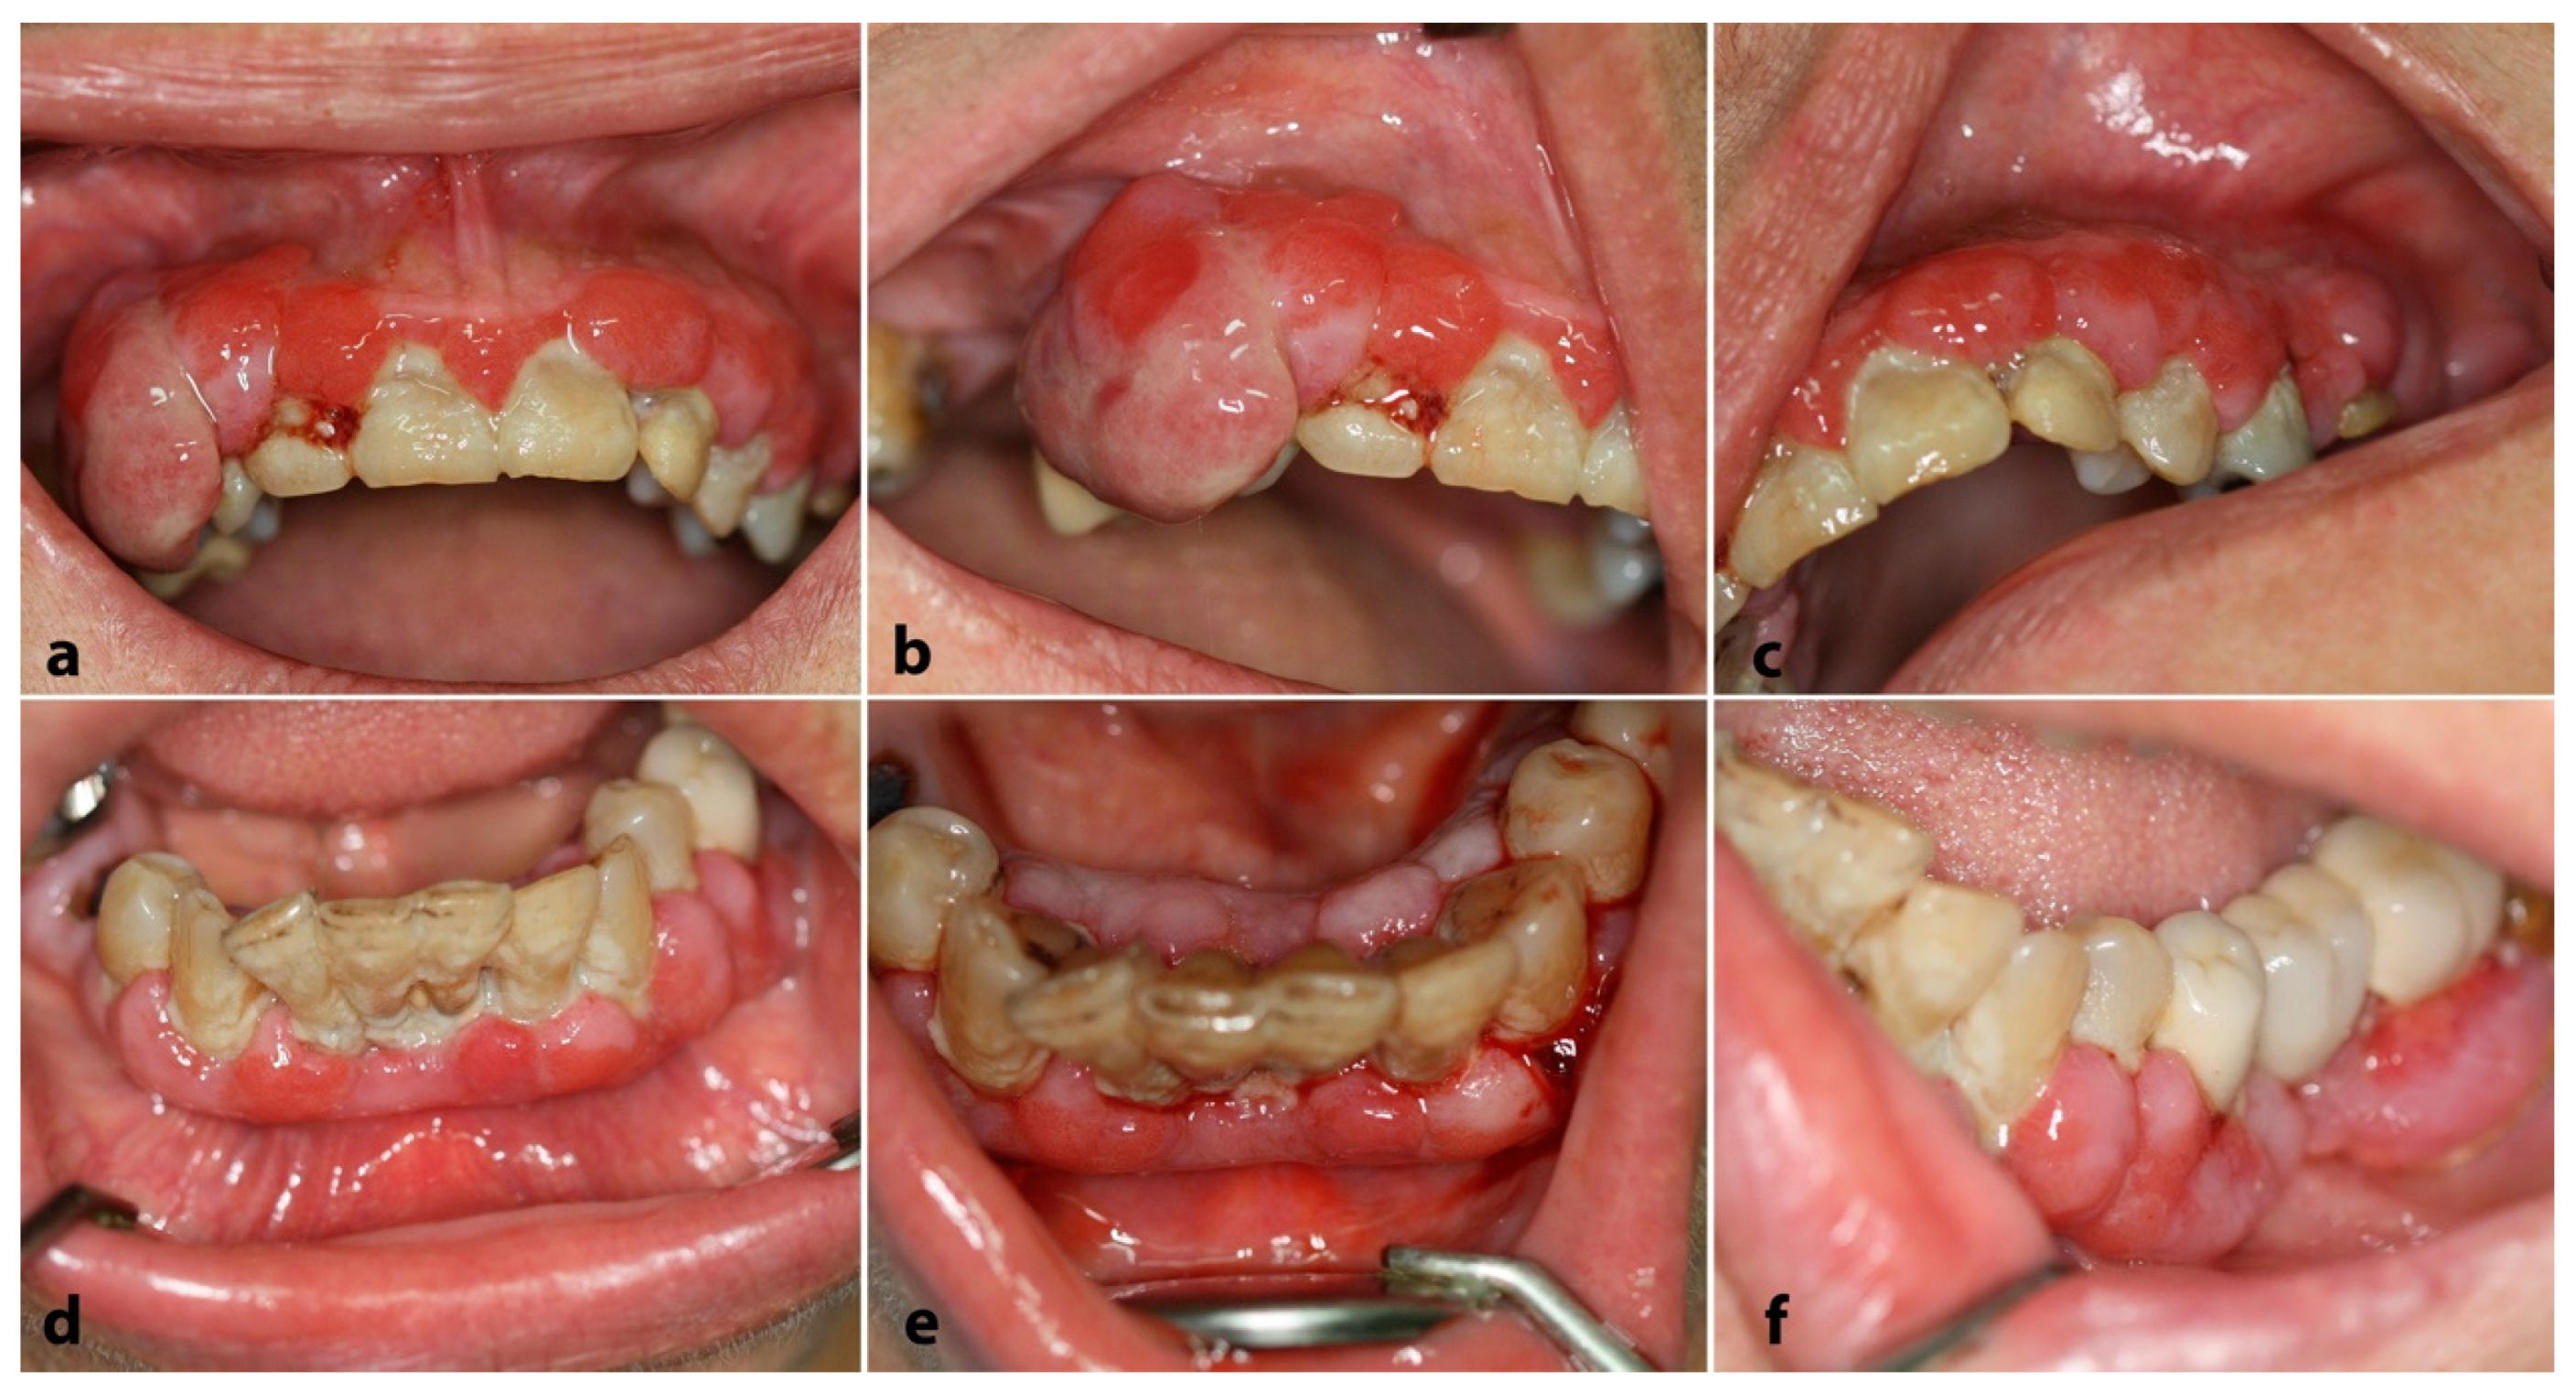

2.1. Case 1

2.2. Case 2